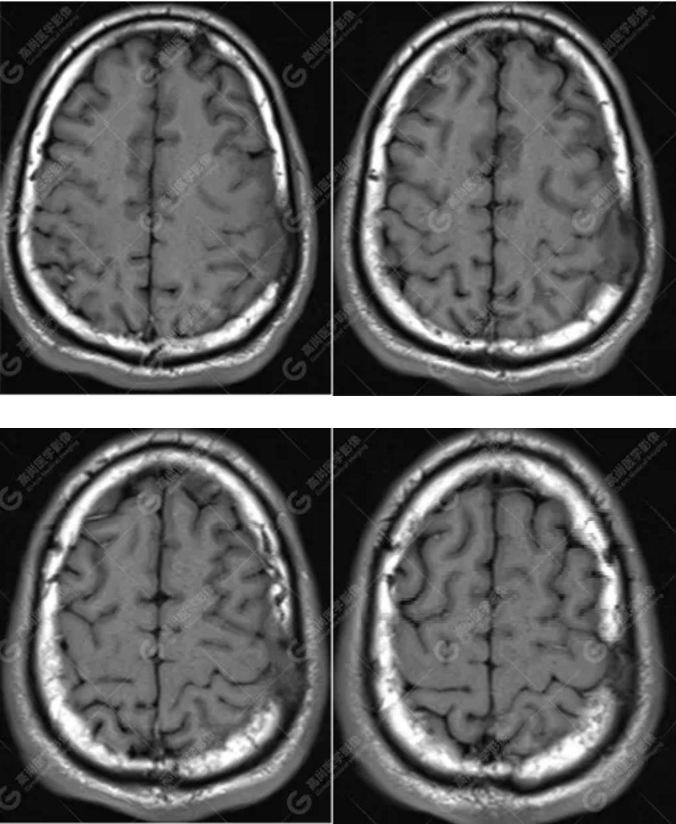

MR圖像

左側(cè)額頂部顱骨骨質(zhì)破壞并相鄰硬腦膜增厚強(qiáng)化,考慮Rosai Dorfman?。≧DD)可能,需與朗格漢斯細(xì)胞組織細(xì)胞增生癥鑒別。

典型的RDD在MRI上T1WI 呈等信號(hào),T2WI及 DWI為等-低信號(hào),增強(qiáng)掃描多為明顯均勻強(qiáng)化,多伴有腦膜尾征,部分病例伴有不同程度的腦水腫。T2WI 像 RDD 病灶中出現(xiàn)聚集的低信號(hào)影及 CT檢查沒有鈣化是 RDD 的特征性影像學(xué)表現(xiàn)。